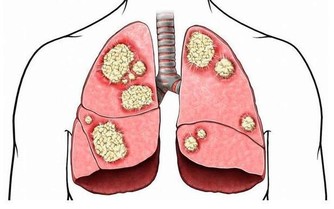

如果放著不管,有些養分和氧氣不能有效到達周邊細胞,就會面臨細胞死亡,而且血液粘稠容易引起血管擁堵,但剛開始發作的時候,並沒有什麼明顯標誌的信號,很容易造成大家的忽視,一般輕者會有頭暈,容易忘東西,腰疼長斑皺紋,失眠,體寒等症狀,嚴重的就會出現動脈硬化,引起心肌梗塞,甚至還會引起腦中風現象。